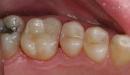

تُعد مشكلة تراكم الأسنان فوق بعضها أو ما يُعرف بالازدحام (بالإنجليزية: Crowding) هي المشكلة الأكثر شيوعًا التي تتطلب استخدام تقويم الأسنان لدى البالغيين والأطفال، وفي سياق الحديث يجدر التنويه إلى أنّ هذه المشكلة تحدث في حال عدم توفر مساحة كافية داخل الفم لنمو جميع الأسنان، وفي الحقيقة فإنّ تراكم الأسنان يزداد سوءًا مع مرور الوقت، إذ قد يؤدي إلى ظهور مناطق في الفم يصعب تنظيفها باستخدام فرشاة الأسنان أو الخيط مما يُسبب تراكم اللويحات السنية (بالإنجليزية: Dental plaque)، والذي يؤدي بدوره إلى تسوس الأسنان، أو رائحة الفم الكريهة، أو أمراض اللثة المختلفة، أو فقدان العظام حول الأسنان، ولحسن الحظ فإنّ تقويم الأسنان يُساعد بشكلٍ كبير في علاج تراكم الأسنان لدى البالغين.[١]

- ازدحام الأسنان: في بعض الحالات قد يمتلك الشخص فكًا ضيقًا، مما يسبب تزاحم الأسنان واضطراب مظهرها ووظائفها، وفي هذه الحالة قد يحتاج الطبيب إلى إزالة بعض الأسنان لفتح المجال للأسنان الأخرى عند وضع التقويم.